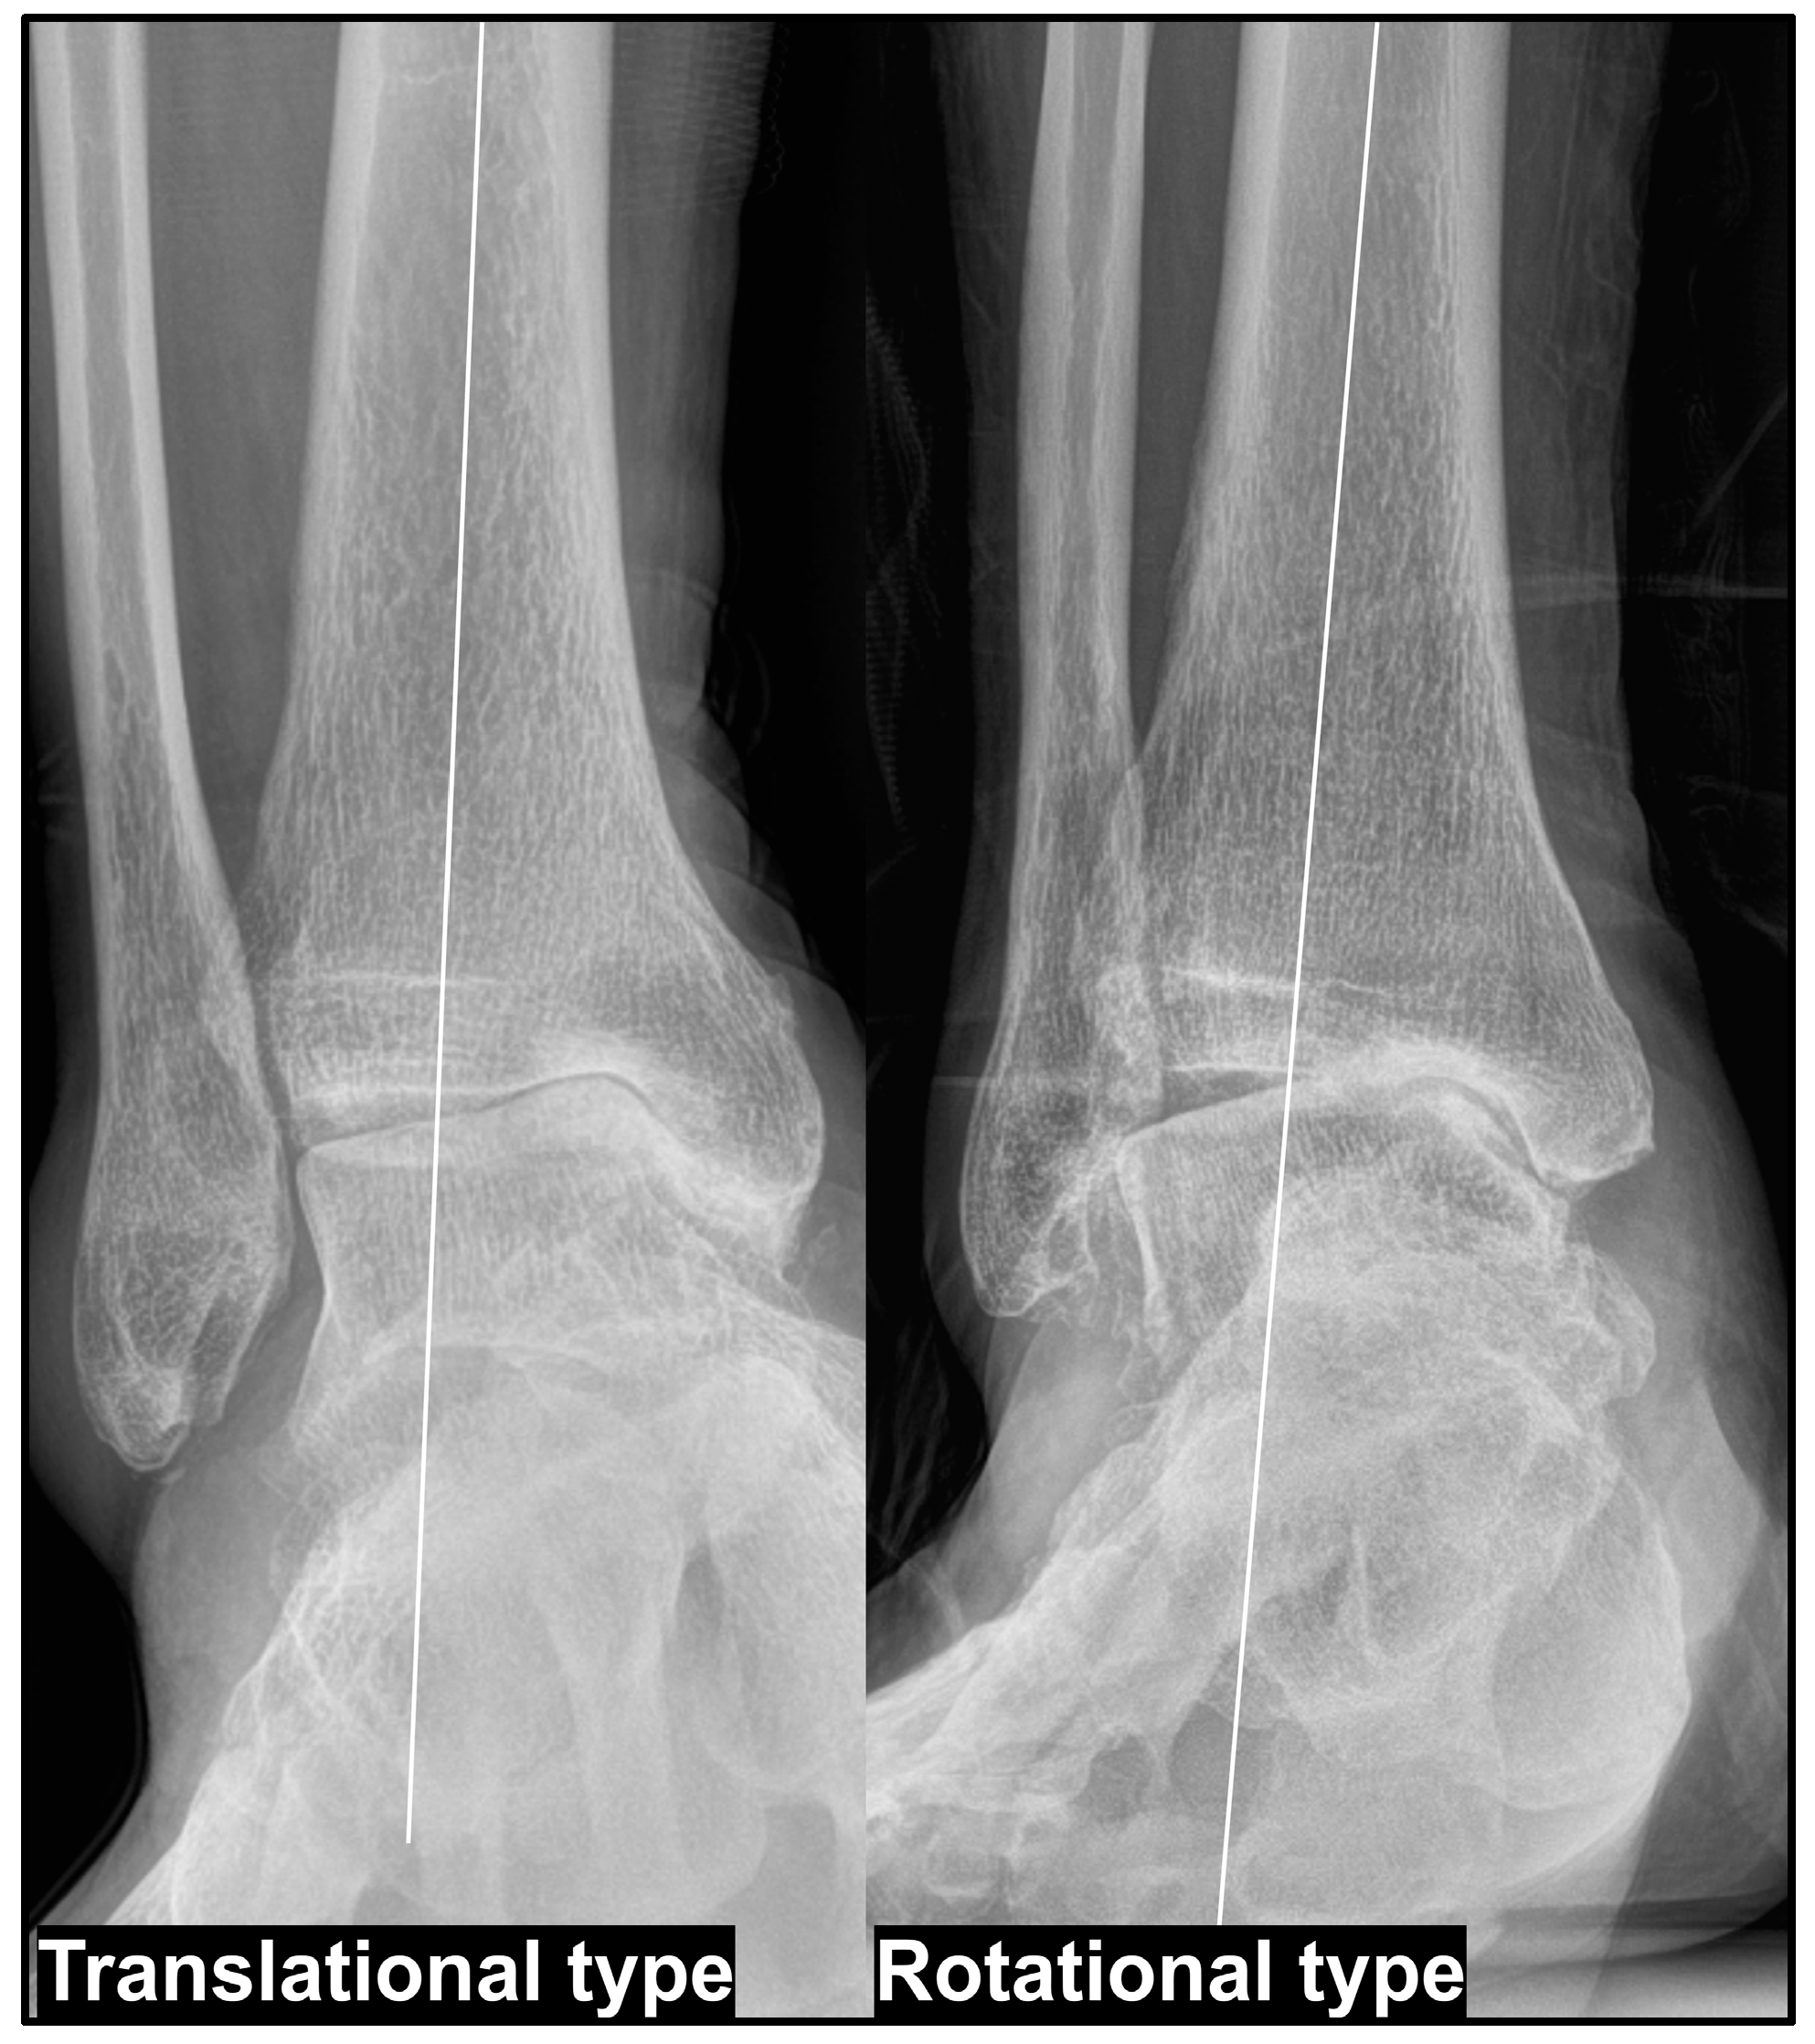

- Choi, W.; Chung, C.Y.; Park, M.S.; Lee, S.; Lee, K.M. Radiographic differences in the concomitant deformities in two types of medial ankle osteoarthritis. PLoS ONE 2021, 16, e0247816. [Google Scholar] [CrossRef]